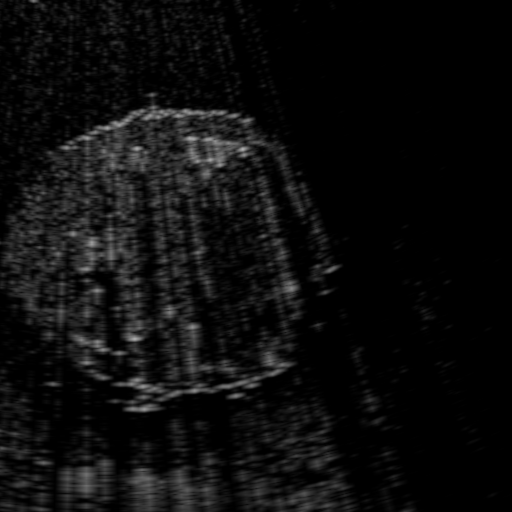

Qualitative Results. Fig. 3 shows a visual comparison of the three model variants on four examples. The baseline L2HM fails to preserve anatomical structures due to missing structural information in the input images. Resulting ambiguities in the network prediction cause artifacts such as blur in regions that feature fine details such as bones. Providing segmentation maps as additional input (L2HMS) greatly reduces such artifacts as shown in Fig. 3(c). However, L2HMS still struggles in modeling complex non-local features such as directional occlusion artifacts, note the lack of acoustic shadows in Fig. 3(c). In contrast, our final model L2HMSA is able to accurately synthesize these features and produces translations significantly closer to the target, as demonstrated in Fig. 3(d). In particular, our proposed model with segmentation and attenuation integral maps is able to recover both missing anatomical structures and directional artefacts.

Above image translation has been demonstrated on patches. For the entire field-of-view (FoV) US images, patch fusion from image translation of non-overlapping patches would cause artifacts at image seams. Averaging overlapping patches, on the other hand, would blur the essential US texture. Although seamless tiling of US images is possible using graphical models [3], this requires prohibitively long computation time. Herein, we instead directly apply our trained generator on full FoV low-quality images, since the generator is fully convolutional and thus can operate on images of arbitrary size. Fig. 4 shows two examples of translated images by L2HMS and L2HMSA, demonstrating direct inference on full FoV images. While anatomical structures are well preserved and the effect of attenuation integral map is apparent, speckle texture appearance is seen to degrade slightly especially in the top image regions, where the ultrasound texture looking particularly different due to focusing difference and near-field effects.

(a) Input

(b) L2HM

(c) L2HMS

(d) L2HMSA

(e) Target